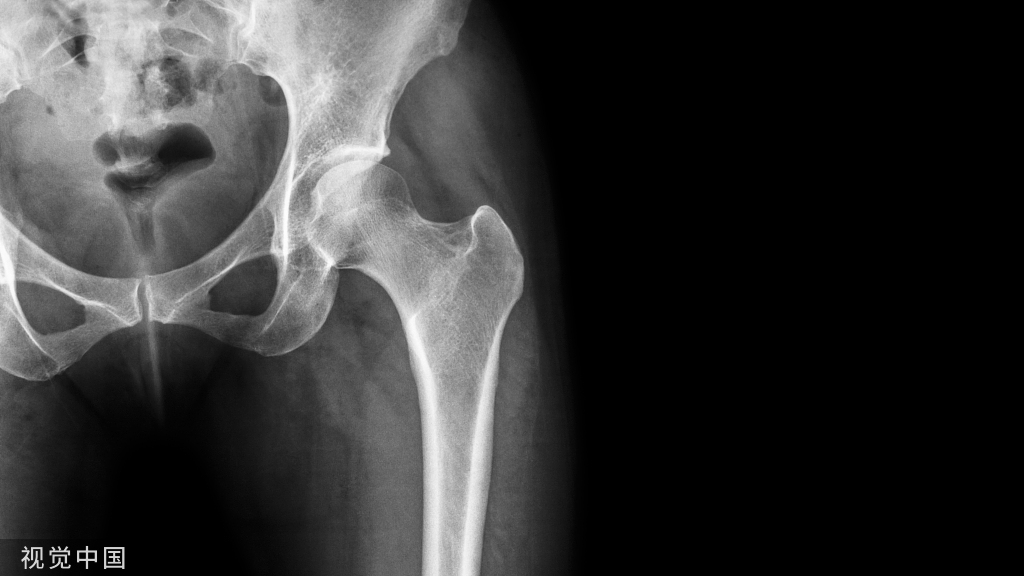

适应证:股骨干广泛外伤、肿瘤或其他病变需彻底切除并需用各种植入物固定者。体位:斜俯卧位,患侧在上。操作步骤:1.将患者的患侧略垫高,在股骨大转子基底部至股骨外髁连线上作纵形切口,后外侧切口则稍靠后(图3(1)(2))。2.沿髂胫束的前缘切开浅筋膜及阔筋膜。将股外侧肌及股中间肌顺肌纤维方向切开。3.于臀大肌前缘切开骨膜,将其自股骨上适当剥离。在进入股骨上1/4段时,可遇到旋股外侧动脉的分支;而在进入股骨下1/4段时,则遇到膝上外动脉,均可切断结扎。必要时,可采用此途径(外侧径路)显露全股骨干,但不如后外侧切口更方便(图3(3))。4.如拟作后外侧切口,应显露股外侧肌的后部,并将其牵向前侧。沿外侧肌间隔的前面继续进行分离直达股骨。外侧肌间隔附着于股骨粗线。将深部组织向前侧牵开,沿切口方向切开骨膜。用骨膜剥离器在骨膜下剥离股中间肌,其范围视需要而定(图3(4))。此途径的缺点是:如患者肌肉发达,股外侧肌较难牵开;此外,在大腿中1/3,从股外侧肌横形穿入的股深动、静脉第2穿支易被切断,应预先结扎、切断。不要分离股二头肌长、短头,以免损伤坐骨神经。

图3 股骨干外侧及后外侧显露径路(1)外侧切口(Ⅰ)及后外侧切口(Ⅱ);(2)横切面显露径路示意图;(3)外侧切口显露股骨;(4)后外侧切口显露股骨。